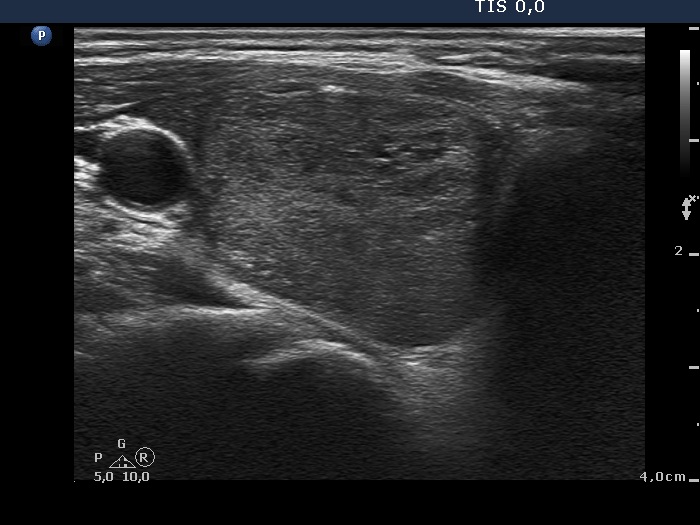

Ultrasonography. The thyroid was echonormal. There was a moderately hypoechogenic nodule in the right lobe. The lesion displayed halo sign and perinodular blood flow.